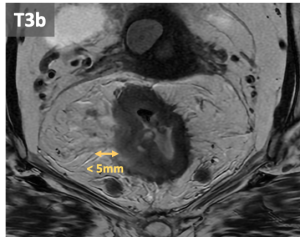

- T3: Tumor extension into the mesorectal fat, beyond muscularis propia. T3 can be subclassified according to the extramural invasion depth:

- T3a: <1 mm

- T3b: 1-5 mm

- T3c: 5-15 mm

- T3d: >15 mmm.